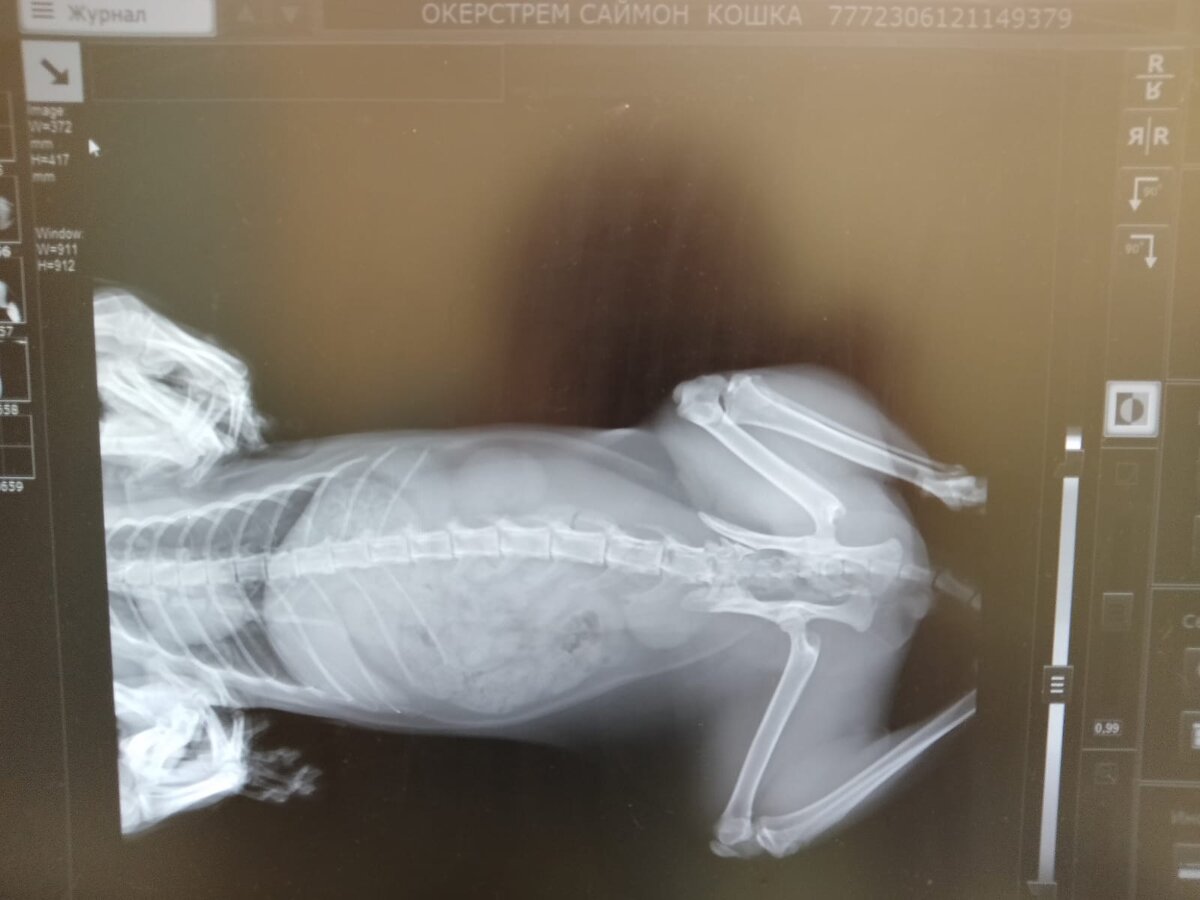

...Сделали рентген , поставили диагноз, Только хирургическое вмешательство !!!

Рентген кота Саймона

Подругин врач, к сожалению , такого не делает, стали обзванивать все Ветклиники и узнавать , где можно такое сделать и сколько это стоит . В итоге, дешевле 💥 100 000 рублей ничего не нашли. Кто - то из знакомых дал контакт Хирурга в Ленинградской области, повезла кота туда ,это 100 км от Санкт-Петербурга , там прекрасная клиника, супер Брутальный мачо-врач, сделал все в лучшем виде за 💥24 000 рублей. Еще и в клинике оставил для дальнейшего ухода.